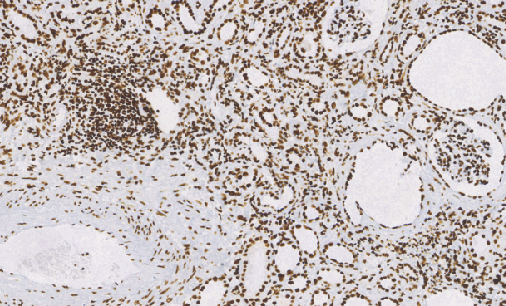

ARID1A是SWI/SNF染色质重塑复合物中的一个亚基,具有DNA结合活性。ARID1A蛋白在肿瘤中频繁缺失,ARID1A基因的突变足以实现肿瘤的发生。此抗体在脾脏,胸腺、前列腺、睾丸、卵巢、小肠和结肠中高度表达,据报道,在卵巢透明细胞癌中,ARID1A蛋白低表达导致低生存率,在宫颈腺癌中,约有9%的阳性率;在子宫内膜癌中有约30%的阳性率。

- 阳性部位:胞核

- 适用组织:石蜡切片

- 预处理:热修复